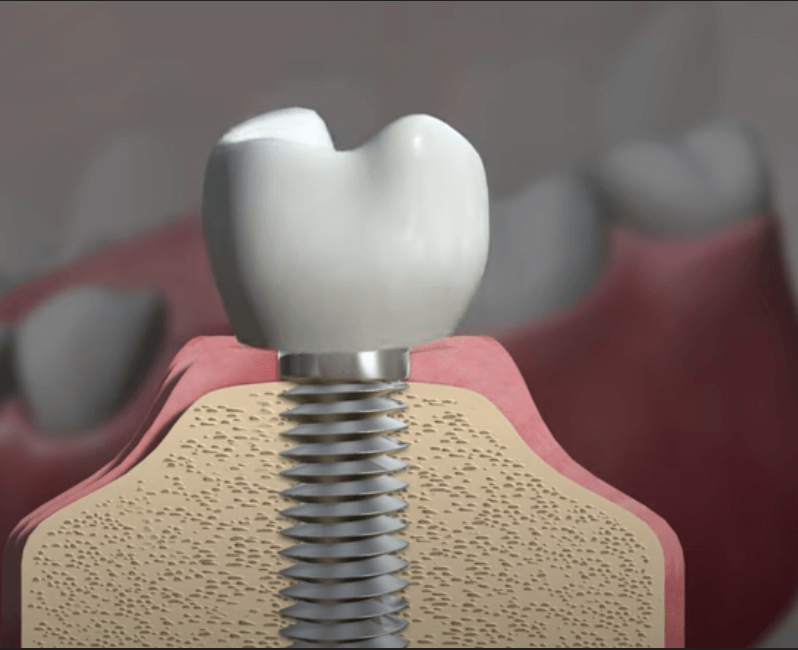

개인적으로 임플란트를 2개를 식립 받은 사람으로 그동안 별다른 부작용 없이 잘 사용하고 있습니다. 임플란트 시술 세계 1위 국가인 국내에서도 대중화가 되며 이를 통해 다시 씹는 즐거움을 되찾은 사람들이 많아지고 있습니다. 하지만 임플란트는 식립이 완료되었다고 해서 모든 과정이 끝나는 것이 아니기 때문에 꾸준히, 지속적으로 관리를 해주는 것이 중요합니다. 만약 관리가 소홀할 경우 잇몸이 녹아내리거나 나사 주변의 염증으로 경우에 따라서는 제거를 하고 브릿지를 해야 하는 경우도 발생하기 때문에 경각심을 가지고 관리하고 주의하는 것이 좋습니다. 오늘은 임플란트 주위염의 원인, 증상, 예방 및 관리방법에 대해서 자세히 살펴보도록 하겠습니다.

임플란트 주위염은 임플란트 수술 후 발생할 수 있는 주요 합병증 중 하나로, 특히 구강 위생이 소홀해지면 자주 나타날 수 있는 증상입니다. 이 질병은 주로 치주에 대한 관리가 부족할 경우 발생하며, 이로 인해 어렵게 심은 임플란트가 뽑히거나 탈락하는 등의 부작용을 유발할 수 있습니다. 임플란트 주위염은 일반적으로 치주염과 유사한 증세를 보이며 초기에는 발견이 어려울 수 있습니다. 이러한 이유로 정기적인 검진이 더욱 중요하며, 초기에 증상을 발견하여 조기에 대처하는 것이 필요합니다.

만약 임플란트가 흔들린다면, 이는 크게 두 가지 주된 원인으로 나뉩니다. 첫 번째로는 임플란트를 구성하는 나사가 헐거워져서 풀어지는 경우입니다. 이 경우에는 나사를 다시 적절히 조이면 문제를 해결할 수 있으며, 비교적 간단한 조치로 신속한 치료가 가능합니다. 그러나 두 번째로, 임플란트 주위염이 원인인 경우에는 상황이 다릅니다. 임플란트 주위염은 임플란트와 치조골 사이의 골 결합이 파괴될 때 발생하며, 이 경우에는 임플란트를 다시 수술하여 재픽싱하는 것이 필요할 수 있습니다. 이는 좀 더 복잡한 치료를 필요로 하며, 빠른 대응이 요구됩니다. 따라서 임플란트의 느슨함이 발견되면, 원인을 신속히 확인하여 적절한 치료 방법을 찾는 것이 중요합니다.

임플란트는 현재로서 자연 치아를 대신할 수 있는 가장 효과적인 방법 중 하나로 인정받고 있습니다. 그러나 임플란트 주위염이 발생하면 임플란트를 제거하고 재식립하는 과정은 간단하지 않기 때문에 초기부터 신중한 관리가 필요합니다. 특히 정기적인 치과 검진이 매우 중요한데, 외부적으로는 문제가 없어 보이더라도 실제로 치조골이 손상되어 있는 경우가 있을 수 있습니다. 따라서 치과 전문의의 꾸준한 감독과 세심한 관리를 통해 임플란트가 오랜 기간 동안 튼튼하게 유지될 수 있도록 하는 것이 핵심입니다.